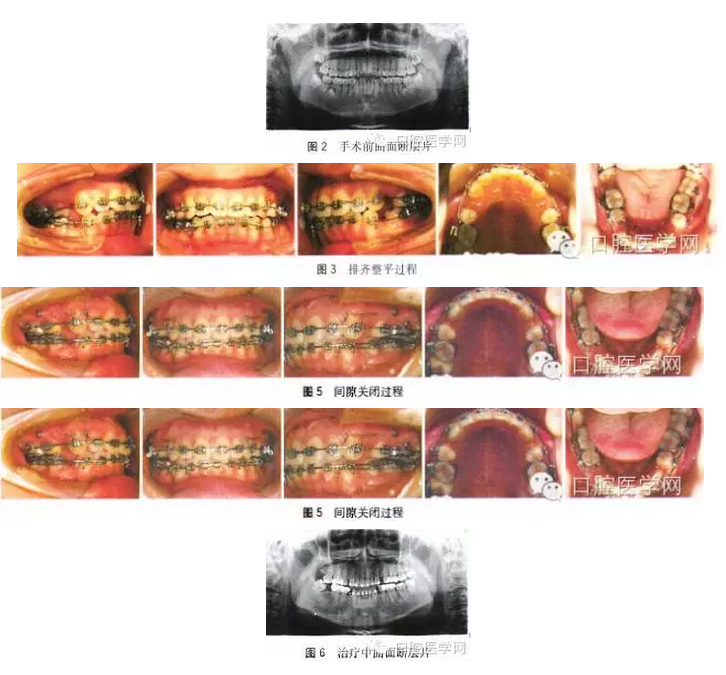

手術(shù)前曲面斷層片:所有恒牙均存在,36、46牙根遠(yuǎn)中各存在一顆多生牙且36、46遠(yuǎn)中根已出現(xiàn)病變吸收,18、28、38、48存在,48近中阻生。手術(shù)后曲面斷層片:所有恒牙均存在,已于外院拔除多生牙,46遠(yuǎn)中根吸收明顯,47近遠(yuǎn)中根基本完全吸收,36遠(yuǎn)中根吸收達(dá)1/2,四顆智齒存在且形態(tài)良好,48近中阻生,頭影測量結(jié)果見表1。

全口粘接0.022英寸(1英寸=2.54 cm)MBT直絲弓固定矯治器,下頜36、45、46帶環(huán),焊接固定舌弓增強(qiáng)支抗,17、27、37粘接頰面管,48牙合面粘接舌側(cè)扣,固定舌弓遠(yuǎn)中拉鉤牽引豎直48,初始弓絲為0.012英寸。待48頰面暴露后粘接頰面管,依次應(yīng)用0.016、0.018、 0.018×0.025英寸鎳鈦方絲初步排齊整平上下牙列并繼續(xù)豎直48。

第 8個(gè)月上頜植入支抗種植釘,更換0.019×0.025英寸不銹鋼方絲,下頜更換0.018×0.025英寸不銹鋼方絲,去除部分固定舌弓但保留45與 46的聯(lián)接,滑動法內(nèi)收前牙并近中移動48。治療過程中48出現(xiàn)舌傾,配合16、17、48交互牽引。第27個(gè)月拔牙間隙關(guān)閉,48移動到位,精細(xì)調(diào)整。第32個(gè)月矯治結(jié)束,上下頜壓膜保持器保持,定期復(fù)查。